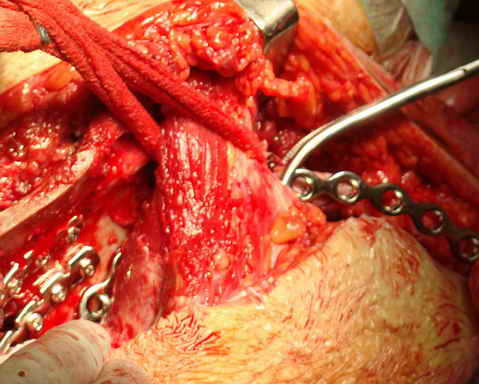

Перелом. Внутритазовый обзор.

Остеосинтез подвздошной кости

уважаемый доктор Атом.....Вам не кажется доступ слишком кровавым и травматичным. ведь осуществляемый вами хирургическицй доступ утяжеляет состояние больного, а кровоточащие сосуды спина илиака увеличивают кровопотерю. А как же хронический ДВС синдром на фоне вашего вмешательства? РО - картина не очень, есть видимость винтов во впадине и ещё какова длительность, столь неоправдано большой операции? Покажите послеоперационную рану? Какие антибиотики вы используете? Время открытой раны?

Уважаемый коллега, не стоит строить утвердительные предложения с выражением "Вам не кажется". Данный хирургический доступ применяется около 8 лет. Помимо того что создаются благоприятные условия для репозиции, сокращается время операции и как следствие - уменьшается кровопотеря, которая составляет около 1 л. при свежих случаях. При застарелых же, по очевидным причинам, существенно выше. Максимальная кровопотеря была 5450 мл. у больного после спленэктомии и давностью травмы более 1 года. Была выполнена одномоментная реконструкция таза с протезированием тазобедренного сустава. Пользуемся Cell Server-ом, производим аутозабор в предоперационном периоде, возвращаем дренажную кровь. ДВС? Тьфу, тьфу, тьфу! Это заслуга АРО и трансфузиологов, и именно они нам позволяют выполнять такие вмешательства.